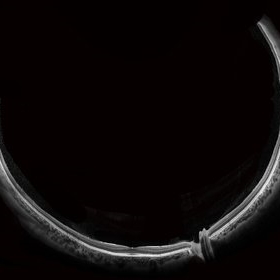

Whole Eye OCT

Jan 4 2019 by Netan Choudhry, MD, FRCS(C) FASRS

Swept-Source OCT montage of a 45-year-old male with Alports disease and posterior subcapsular cataract.

Photographer: John Golding BA, Vitreous Retina Macula Specialists of Toronto

Imaging device: Topcon DRI Triton

Condition/keywords: Alports disease, optical coherence tomography (OCT), swept source